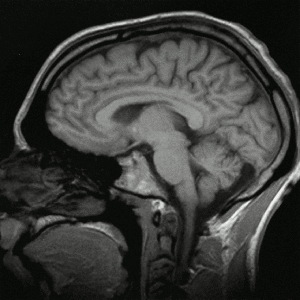

متلازمة الألم المركزية، هي حالة عصبية عضوية سببها عطل النظام العصبي المركزي (سي إن إس) central nervous system (CNS)، الذي يتضمّن الدماغ، النخاع، والحبل الشوكي. مسببات هذه المتلازمة يمكن أن تكون جلطة، تصلّب أنسجة متعدّد، أورام، صرع، ورم الحبل الشوكي أو الدماغ، أو مرض باركنسن. وضع الألم المرتبط بهذه المتلازمة يختلف كثيرا بين الأفراد، جزئيا بسبب إختلاف الأسباب المحتملة. متلازمة الألم المركزية قد تؤثّر على جزء كبير من الجسم أو قد تكون أكثر تأثيرا في مناطق معيّنة، مثل الأيدي أو الأقدام. إنّ مدى الألم مرتبط بسبب الإصابة عادة. الألم ثابت عادة، قد يكون معتدل إلى حاد، ويصبح أسوأ في أغلب الأحيان باللمس، الحركة، العواطف، وتغييرات درجة الحرارة، عادة درجات الحرارة الباردة. يواجه الأفراد نوع أو أكثر من أحاسيس الألم، الأبرز هو إحساس الحرق. قد يختلط بأحساس الإحتراق أحاسيس غزّ الدبابيس؛ الضغط، التمزق، أو الآم لحظية؛ إنفجارات لاتطاق من الألم الحادّ مشابه للألم الذي يسببه لمس ابرة على عصب أسنان مكشوف. المصابين قد يتولد عندهم إحساس بالخدر في المناطق التي أثّر عليها الألم. إنّ إحساس الحرق و فقدان حاسة اللمس، تصيب عادة الأجزاء البعيدة للجسم، مثل الأقدام أو الأيدي. تبدأ متلازمة الألم المركزية في أغلب الأحيان بعد فترة قليلة من الإصابة أو الضرر المسبب، لكن قد يتأخر ظهورها لشهور أو حتى سنوات، خصوصا إذا كانت متعلّقة بألام ما بعد الضربة.